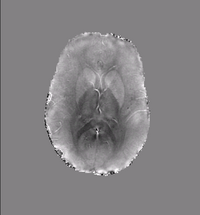

Susceptibility Map 2

Quantifying magnetic susceptibility in the brain from the phase of the MR signal provides a non-invasive means for measuring the accumulation of iron believed to occur with aging and neurodegenerative disease.

We describe a variational approach to susceptibility estimation that incorporates a tissue-air atlas to resolve ambiguity in the susceptibility estimates, while eliminating additional biasfields through application of the Laplacian.

Results show improved correlation with postmortem iron concentrations relative to competing methods.

• Algorithm: Improved background field correction, resulting in improved mean susceptibility values:

Thalamus ( -0.06 ppm )

Caudate (0.02 ppm)

Putamen (0.05 ppm)

Globus Pallidus (0.11 ppm)